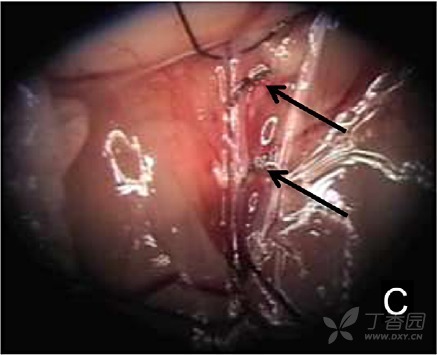

图 C. 用 7-0 丝线结扎股静脉属支(箭头所示)

图 I. 以同样方式吻合供体肺动脉和受体股静脉,注意不要缝到血管内壁(箭头所指),以免供体心脏位置翻转